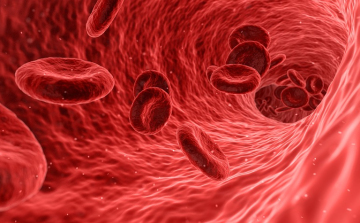

A vérmérgezés kezelésére dolgoznak ki új módszert Szegeden

A szepszis kezelésének hatékonyabb módszerén dolgoznak a Szegedi Tudományegyetem aneszteziológiai és intenzív terápiás intézetének szakemberei Molnár Zsolt professzor vezetésével.